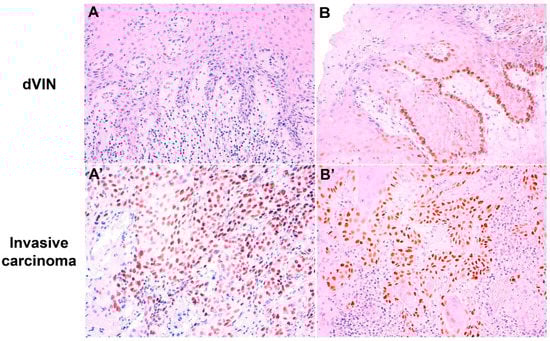

Figure 3.

Two cases with discordant p53 immunohistochemical patterns between intraepithelial lesion and adjacent invasive carcinoma. (A): Differentiated vulvar intraepithelial neoplasia (dVIN) showing wild-type scattered p53 pattern; (A’) invasive carcinoma from the same case with p53 parabasal overexpression; (B): dVIN with p53 basal staining; (B’) invasive component from the same case showing p53 parabasal overexpression (p53 IHC immunostaining with hematoxylin counterstain, original magnification: 100× (A,B,B’) and 200× (A’)).